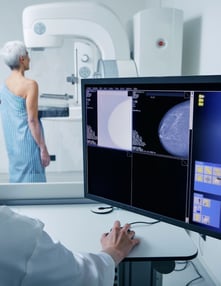

A woman getting a mammogramMammography remains the gold standard in breast cancer screening, but it is not magic. While mammograms reveal important visual clues about breast tissue, they cannot always provide a definitive diagnosis.  That is why radiologists rely on specific image features, follow-up imaging, and additional tools to distinguish between benign and suspicious findings.

We asked Dr. Tchaiko Parris, MD, PhD, Director of Mammography and Breast Cancer Prevention at ImageONE, to explain how mammograms are interpreted and what clinicians can do to support clearer, more confident readings.